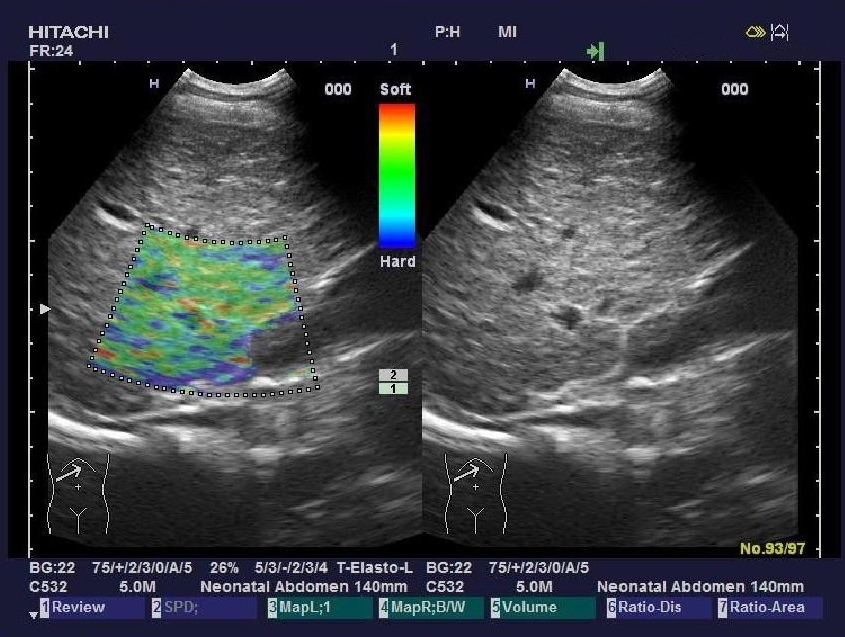

實(shí)時(shí)組織彈性成像技術(shù)

(Real-time Tissue Elastography)

“ARIETTA 70”加載了彈性成像功能,實(shí)時(shí)組織彈性成像技術(shù)是根據(jù)人體不同組織受壓后的變形差別,將其不同的組織的彈 性系數(shù)差異用不同的彩色顯示出來的新成像診斷技術(shù)。

組織彈性成像技術(shù)完全脫離了常規(guī)超聲聲阻抗成像原理,開辟了超聲診斷原理的新領(lǐng)域。將指尖的觸診高速信息化數(shù)字化,不 僅實(shí)現(xiàn)了定性分析,還具備定量分析功能。

臨床應(yīng)用領(lǐng)域:乳腺、甲狀腺、前列腺、皮膚、肝臟、子宮、卵巢、胰 腺、淋巴結(jié)、血管、直腸、睪丸、顱腦及多種術(shù)中檢查。